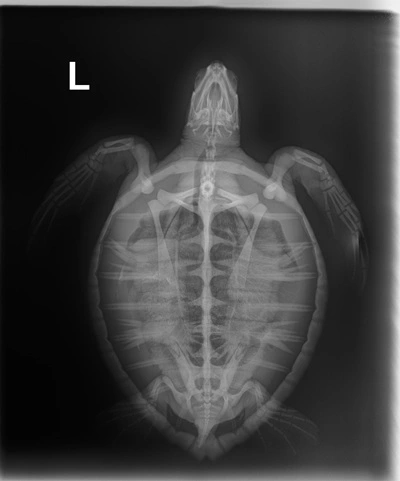

1.95 kg juvenile Atlantic Green sea turtle

Patient Injuries

External Carapace Notes: one small abrasion on carapace

Plastron: moderate abrasions

Head/Flippers/Soft Tissue: abrasions on both front flippers and both sides of head